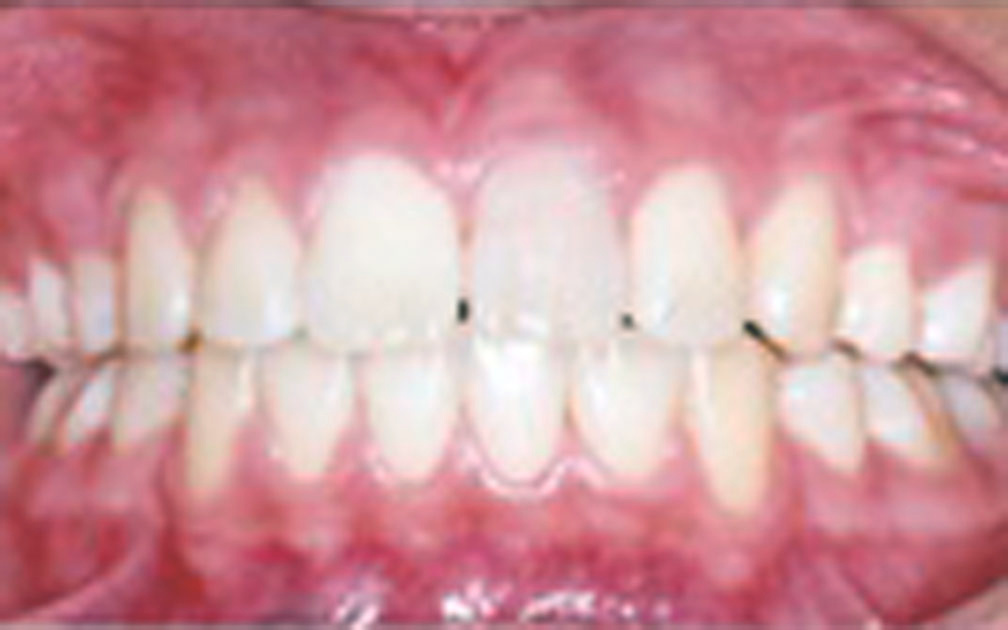

矯正の症例5 (診断名)下顎前突(カガクゼントツ)(外科的矯正有)

(患者様の主訴)前歯で噛めない

(治療開始年齢)28歳0カ月

(主な治療装置)エッジワイズアプライアンス 外科的矯正治療

(抜歯部位)非抜歯

(治療期間)4年7カ月

(治療費)¥266990

(個別リスク・副作用)外科的矯正治療で長期にわたりブラケットを装着しているため齲蝕になるリスクがある。

初診時より低位舌が強いため、矯正治療後に下顎が広がりやすく安定したかみ合わせを得にくいというリスクがある。そのため治療後下顎の幅が広がらないように長期にわたり保定装置を装着する必要がある